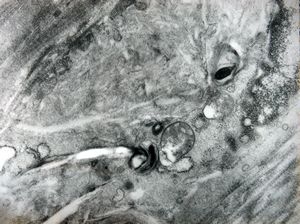

M,15y. | neurinoma n. optici